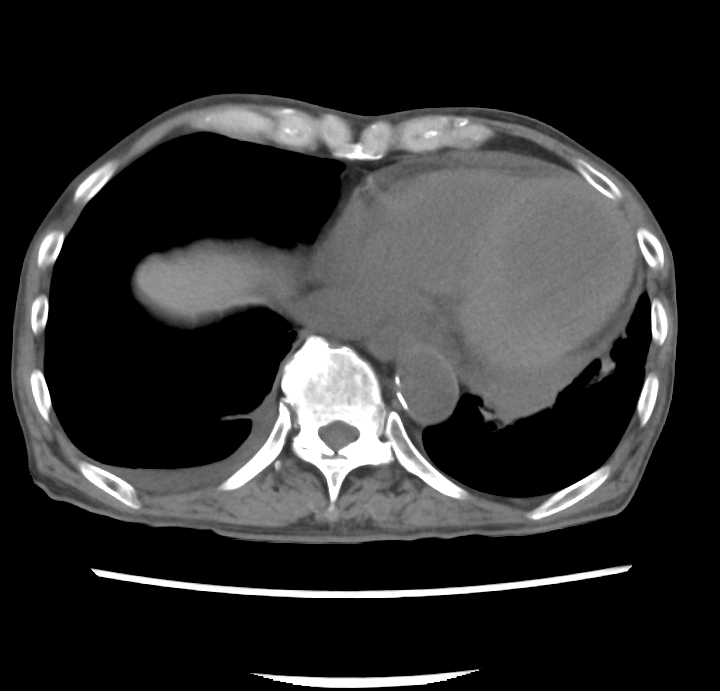

意識障害と発熱の精査加療目的に入院.低血糖(6 mg/dL)の補正により意識障害はすみやかに改善した.CTおよび超音波内視鏡検査にて総胆管結石による胆石性胆管炎が発熱の原因と考えられ,内視鏡的採石術および内視鏡的乳頭括約筋切開術(endoscopic sphincterotomy:EST)を施行された.入院6日目に血便と貧血の進行および血圧低下があり原因検索目的に造影CTを施行した.

1. Q1:非造影CT(図1A)で血腫の存在が疑われる部位は?

図1 A)非造影CT 連続画像

誌面掲載画像は赤枠で示す